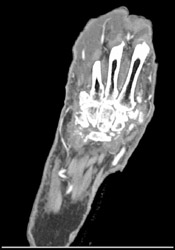

Tibial, Fibular, and Femoral Fractures